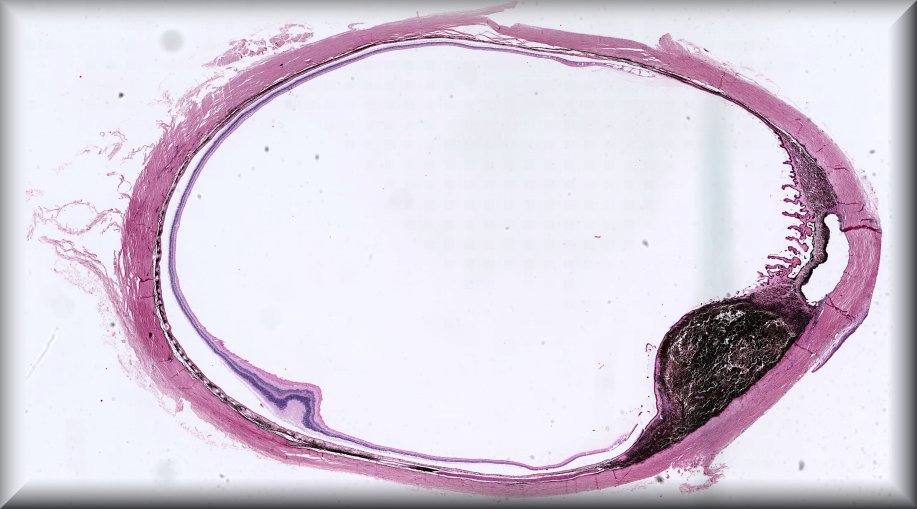

Dietmar Thal (Leuven): Eyeball resection for melanoma in an 83-year old male Alzheimer's disease patient |